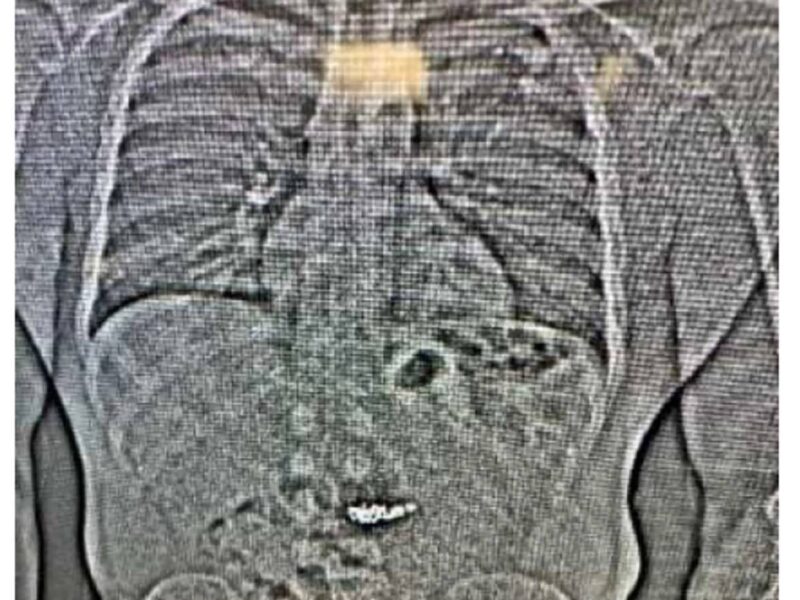

After his arrest, Gilder swallowed several items, later identified through a scan at Washington County Jail as the missing Tiffany & Co. earrings. Officers also found price tags, earring forms, receipts, and clothing matching what he had worn during the robbery inside the car.